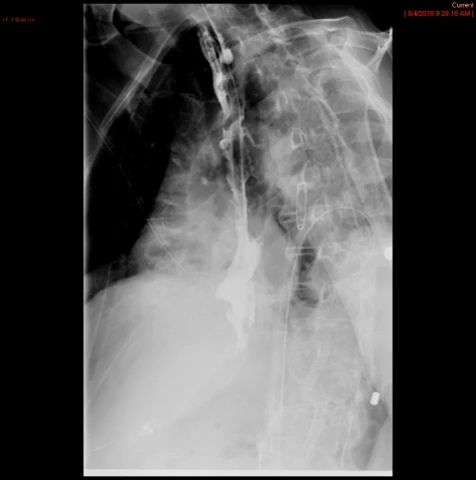

- The technologist will obtain a scout radiograph(s) to include the chest and upper abdomen to determine the location of the surgical chain sutures or surgical staples

(key image 1).

- The esophagogastric anastomosis is usually located at the level of the aortic arch or just below it.